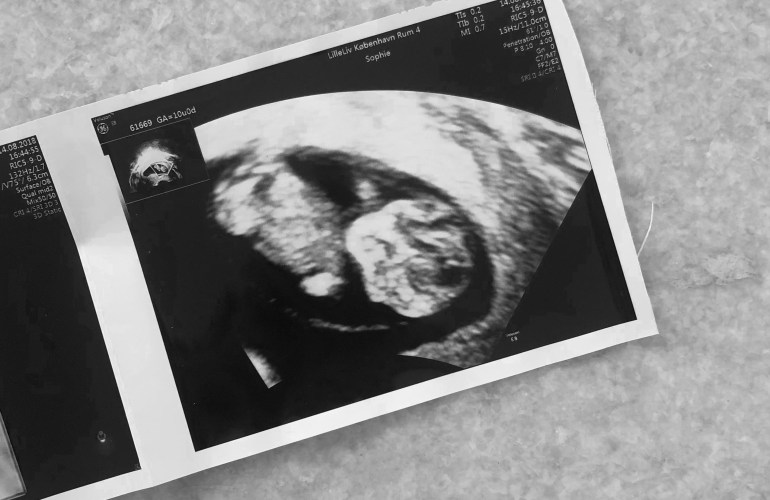

Selvom det var første gang jeg nogensinde skulle have en ultralydsscanning og se et barn i min mave, føltes det som det mest naturlige i verden. Jeg lagde mig til rette på briksen, trak lidt ned i mine cowboybukser og Martin satte sig i den store lænestol ved siden af og tog min hånd. For enden af briksen var en stor skærm, hvor vi kunne følge med i scanningen. Hun advarede mig om det kolde gele og smurte min mave forsigtigt ind, inden hun satte scanneren på. Og lige dér lå vores lille vidunder. Den lillebitte baby lå på siden med ryggen mod os, så vi kunne se den søde numse og de små ben, som han havde trukket op under sig. (På det tidspunkt vidste vi selvfølgelig intet om at det var en lille dreng der lå derinde og moonede til os).

I 10 minutter holdt vi i hånden og kiggede bare på en kidneybønne, der boblede rundt. En kidneybønne, der dengang var 9+4 uger gammel. Da vi var færdige tørrede hun geléen af min mave med et lille varmt håndklæde. Hun trykkede os begge i hånden og sagde tillykke med vores fine lille baby, før hun forlod rummet og gav os god tid til at samle vores ting.

Da vi kom ud til skranken lå en fin lyselilla mappe klar med dokumenter, der indeholdte al information fra scanningen. Der var målene på vores baby, mit navn og cpr-nummer og nogle andre ting, som jeg ikke helt vidste hvad var. Der var også nogle postkort, men vigtigst af alt, var scanningsbillederne og et link, hvor vi kunne se en video af vores lille baby-Blob boble rundt i min mave. Den video så jeg på flere gange de næste mange uger, hver gang jeg savnede et glimt ind i maven.

Dagen efter scanningen kom vores forældre og søskende forbi til middag. Jeg var simpelthen så spændt på at fortælle dem, at der var en lille Blob inde i min mave. I to små æsker havde vi lagt et scanningsbillede, som vi fik med fra privatklinikken i Gothersgade. Æskerne blev overrakt til vores mødre, som jeg helt ærligt ikke tror havde fattet nogen form for mistanke forinden. Utroligt nok. Der blev helt stille omkring bordet, mens de synkront forsigtigt åbnede æskerne. Jeg sad overfor min mor og fulgte med i hvordan hendes øjne pludseligt blev lige så store som tekopper, ligesom hendes mund. Hun kiggede på mig og sagde “Er det rigtigt?!” og nærmest grinede af overraskelse. Min svigerfar som sad i den anden ende af bordet mumlede noget i retning af “Det havde jeg da regnet ud for længst”.. Okay, så siger vi det, du gamle (;